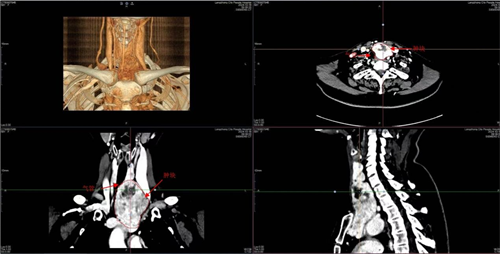

陈阿姨在5年前体检时查出甲状腺左侧叶结节,大小为2.5×1.6cm。由于平时无特殊不适症状,便未作进一步治疗。然而,2024年10月,当陈阿姨前往阆中市人民医院甲乳肛肠科门诊复查时,情况却发生了巨大变化。颈部CT检查显示:甲状腺左侧叶巨大肿瘤,大小为10.0×6.0cm。该肿瘤位于胸骨后,与左颈总动脉、左头臂静脉及左颈内静脉相邻,气管明显受压移位。

办理入院后,甲乳肛肠科团队对其进行了详细的术前评估。鉴于肿瘤位于胸骨后这一特殊位置,且与周围血管神经关系密切,术中出现大出血、神经损伤等风险极高。而且,气管长期受挤压变形还可能导致气管软化,术后有塌陷窒息等风险。

手术在全麻状态下进行,麻醉科凭借丰富的狭窄气道管理临床经验,一次性完成气管插管工作,为后续手术提供了充分的安全保障。在甲乳肛肠科主任屈军的指导下,唐涛博士团队为患者实施了“甲状腺左叶及胸骨后巨大甲状腺肿切除+甲状腺右叶良性结节切除手术”。术中情况与术前预判一致,肿瘤大部分位于胸骨后,导致气管推挤受压明显,且瘤体血供丰富与左头臂静脉、静内静脉粘连,手术风险较大。